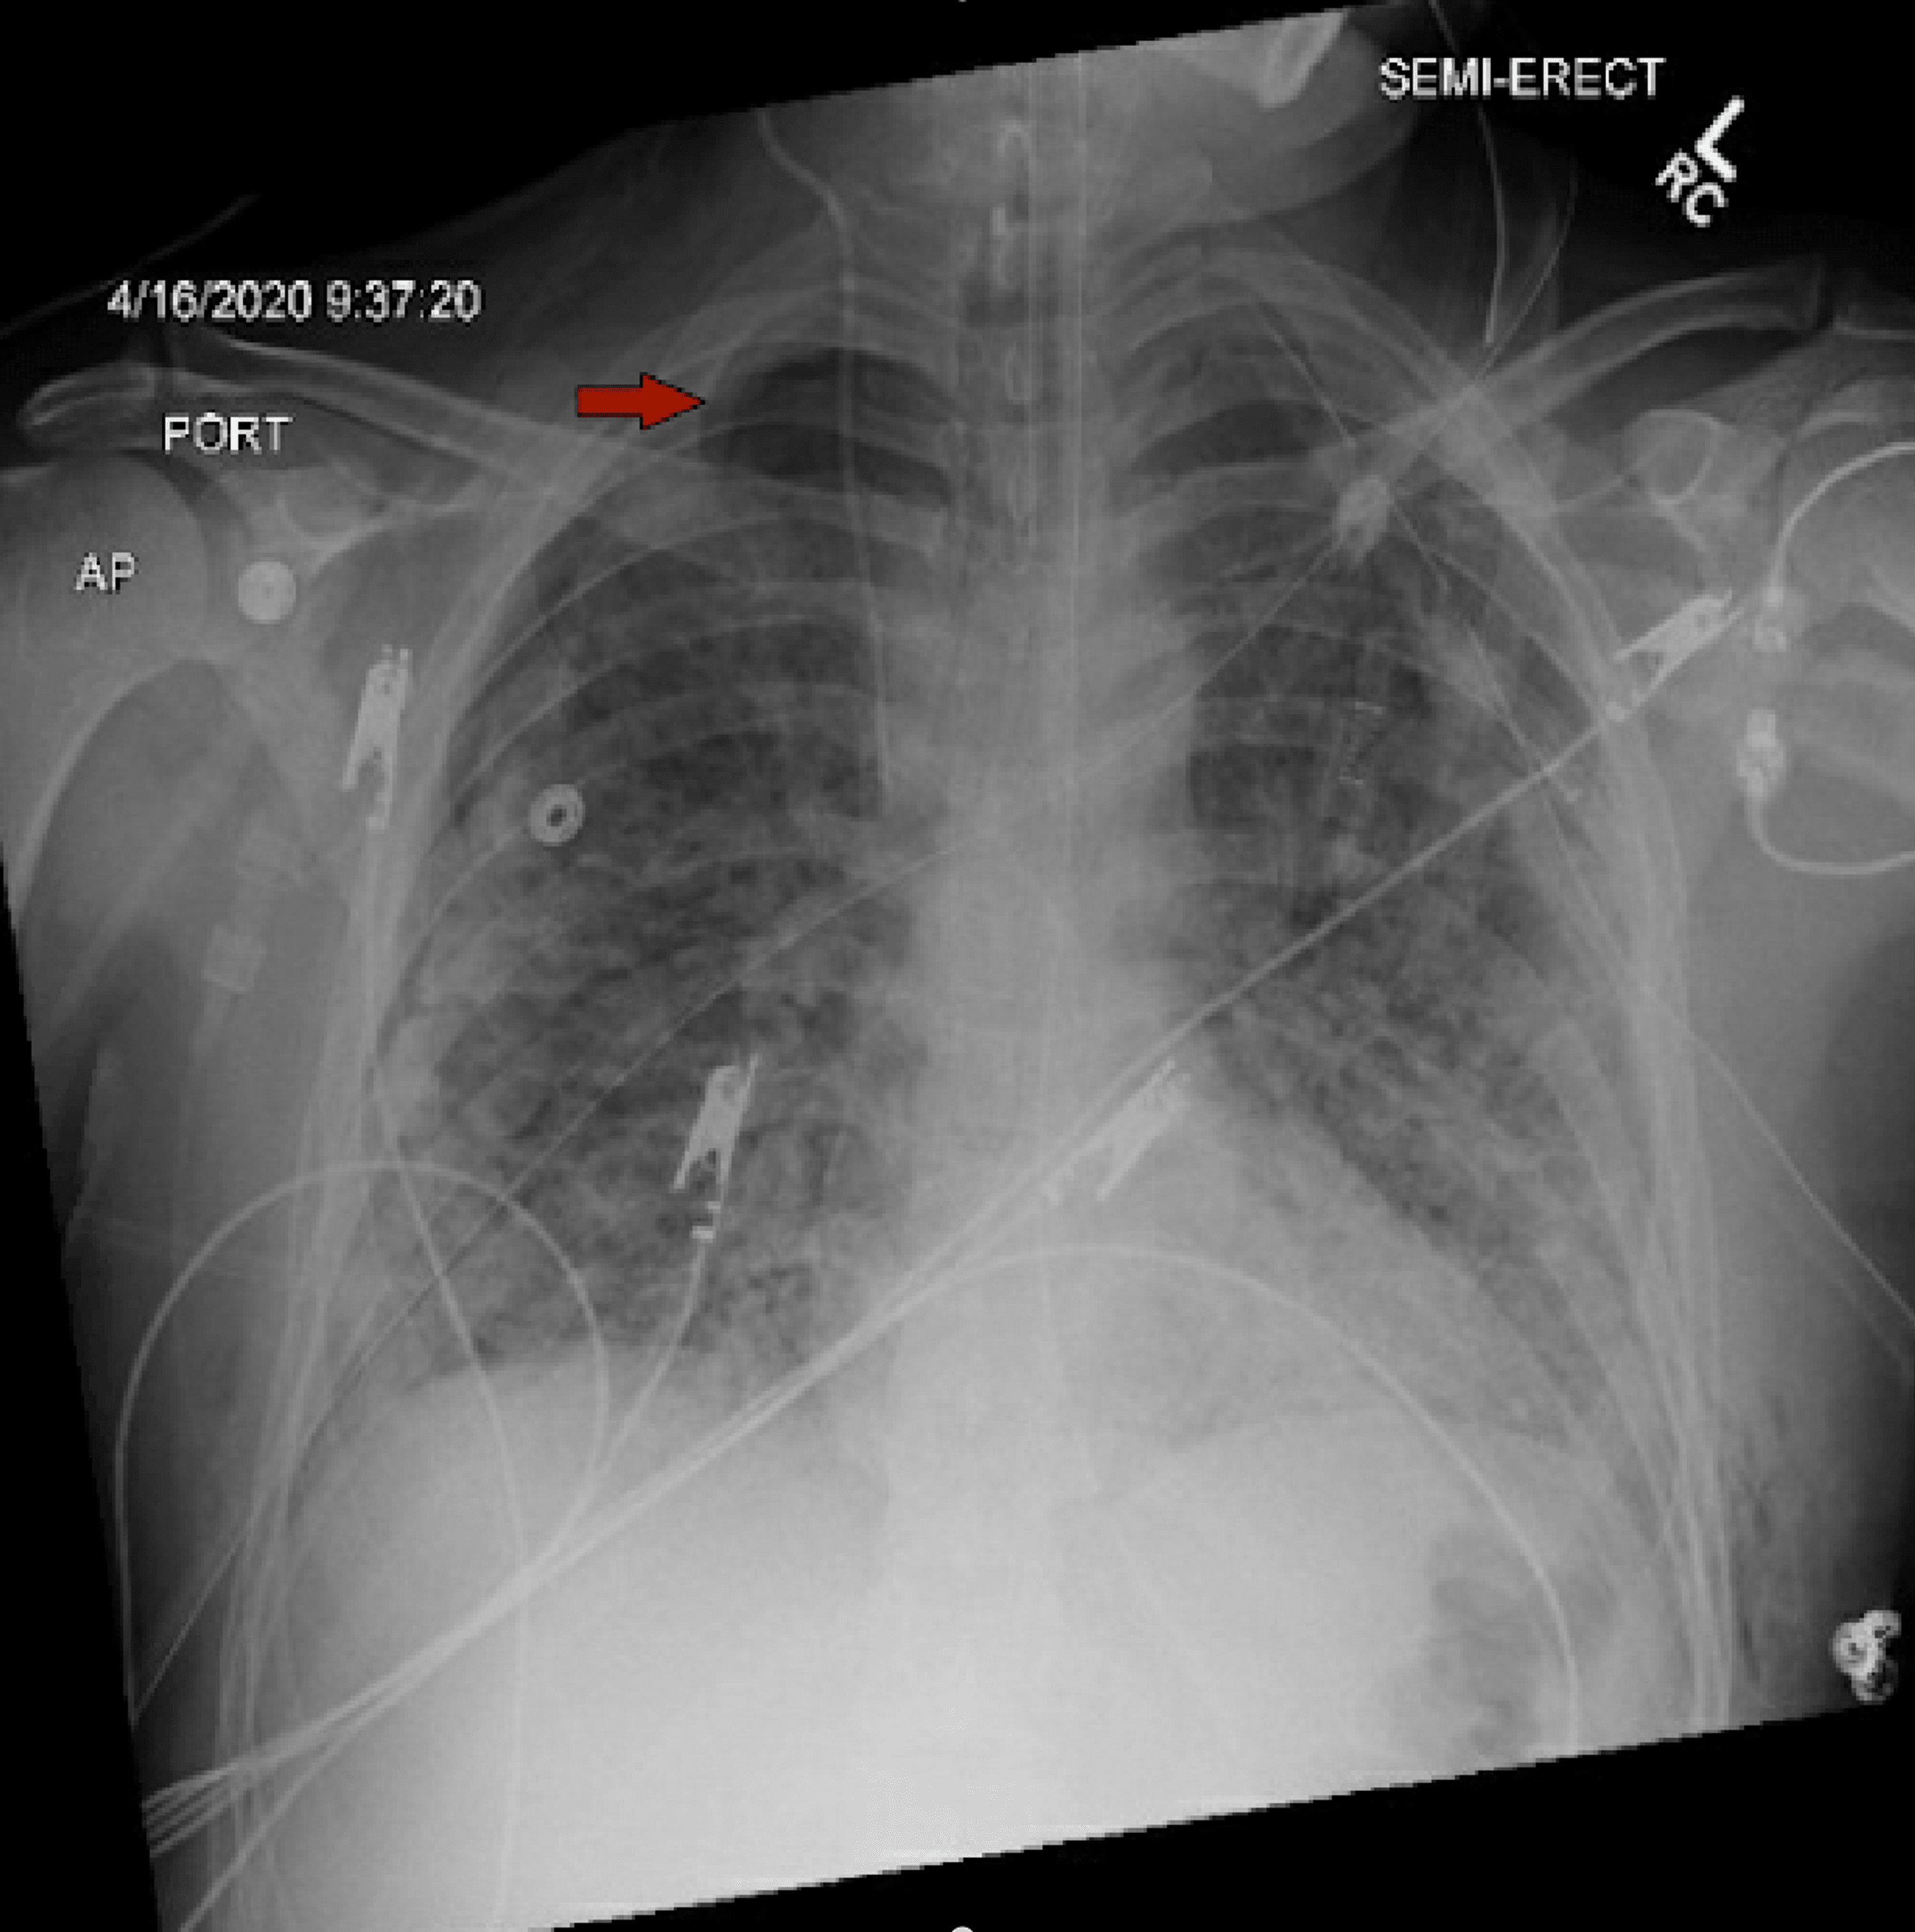

Cureus Pneumothorax in Intubated Patients With COVID19 A Case Series Intubation And Pneumothorax pneumothorax is a potentially lethal complication associated with. the duration of chest intubation among those with pneumothorax varied between 2 and 15 days (median 7). historically, a small pneumothorax has been shown to be successfully treated without chest tube. pneumothorax is especially likely if there is right main bronchus intubation. Intubation And Pneumothorax.

Cureus Pneumothorax in Intubated Patients With COVID19 A Case Series Intubation And Pneumothorax pneumothorax is a potentially lethal complication associated with. historically, a small pneumothorax has been shown to be successfully treated without chest tube. the duration of chest intubation among those with pneumothorax varied between 2 and 15 days (median 7). pneumothorax is especially likely if there is right main bronchus intubation. Intubation And Pneumothorax.